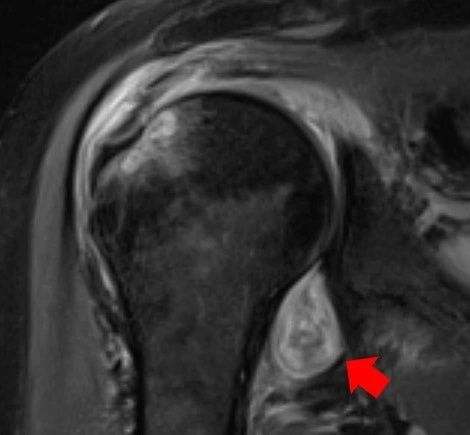

Przeanalizowali oni wyniki badań pacjentów z COVID-19, którzy zgłosili się do Northwestern Memorial Hospital od maja do grudnia 2020 roku. Część osób, u których wystąpiły długotrwałe powikłania, miała przeprowadzone rezonans magnetyczny, tomografię komputerową lub USG. Mając obrazy radiologiczne, naukowcy byli w stanie określić pochodzenie i charakter objawów. Wyniki badań zostały opublikowane na łamach czasopisma "Skeletal Radiology".

Dzięki obrazom radiologicznym, naukowcy byli w stanie określić pochodzenie i charakter objawów.

"Nowoczesne metody obrazowania pozwoliły nam zobaczyć, że bóle stawów i mięśni związane z COVID-19 są podobne do tych, które odczuwamy podczas grypy, ale stoi za nimi znacznie bardziej podstępny mechanizm" - opowiada dr Deshmukh.